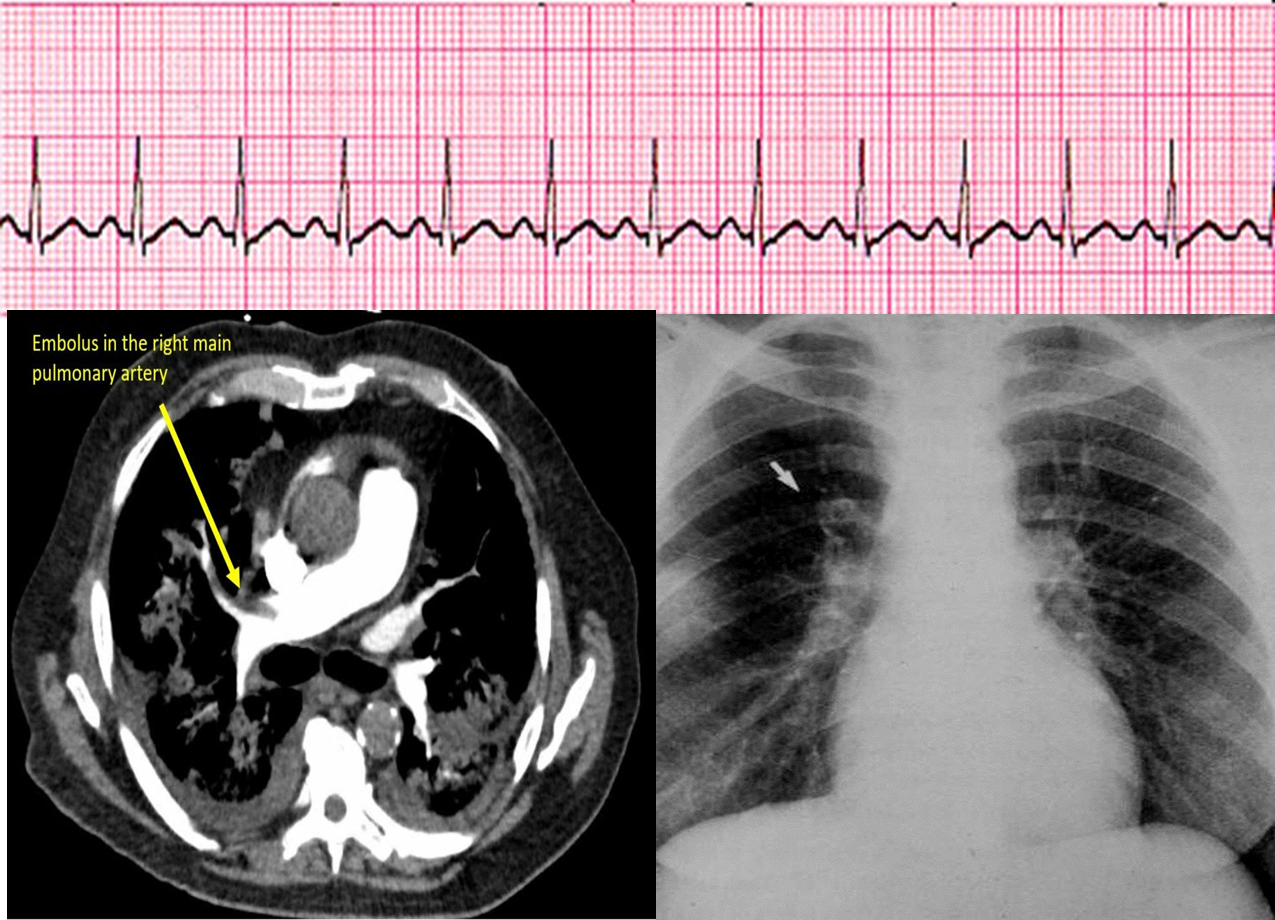

- ECG; sinus tachycardia, S1 Q3 T3

- Chest x-ray (West hamptom palla signs) - CT

What will you do next? ECG. X-RAY. CT.

What is your diagnosis Acute Pulmonary Embolism

Pulmonary Angiography (GOLD STANDARD)

•Arrow indicates abrupt termination of a pulmonary artery.